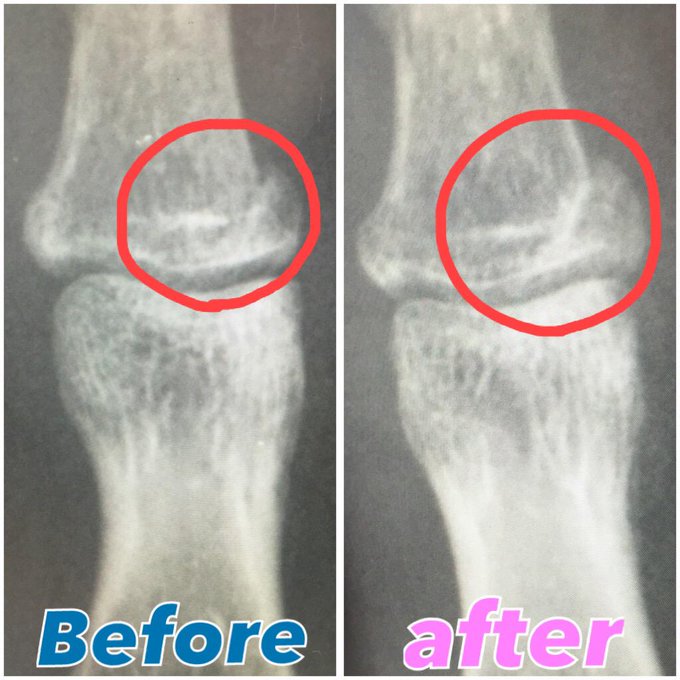

【朗報】三田氏ギブスがとれる

まだ完治とはいきませんが、ギブスがとれましたー!これから少しずつ動かす練習をしていきます!

一ヶ月の固定で関節が固まってたりするからね👍

5周年に間に合いそうでよかったよかった🙏